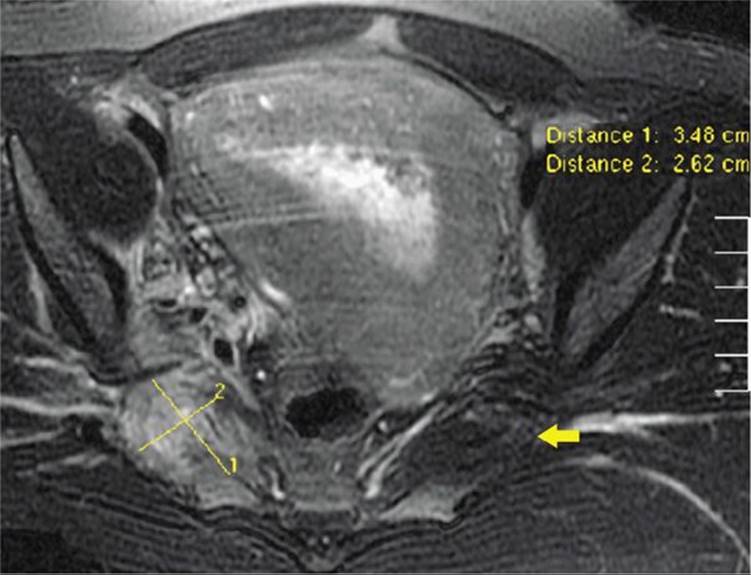

Pain in the pelvic girdle, hips, or lower extremities may follow stretching or tearing injuries sustained at normal or difficult delivery. Magnetic resonance (MR) imaging is often informative. One example is the piriformis muscle hematoma shown in Figure 36-6. Most injuries resolve with antiinflammatory agents and physical therapy. Rarely, there may be septic pyomyositis such as with iliopsoas muscle abscess (Nelson, 2010; Young, 2010).

FIGURE 36-6 Magnetic resonance image of a piriformis hematoma. A large inhomogeneous mass of the right piriformis muscle consistent with a hematoma (yellow cursor measurements) is compared with the normal-appearing left piriformis muscle (yellow arrow).